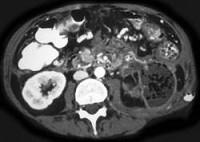

问题 女性,34岁,寒战、高热、急性中上腹偏左腹痛,压痛,CT扫描如图,最可能的诊断是 ( )

选项 A.急性胰腺炎 B.胰腺脓肿 C.慢性胰腺炎急性发作 D.胰腺癌 E.胰腺转移癌

答案 B